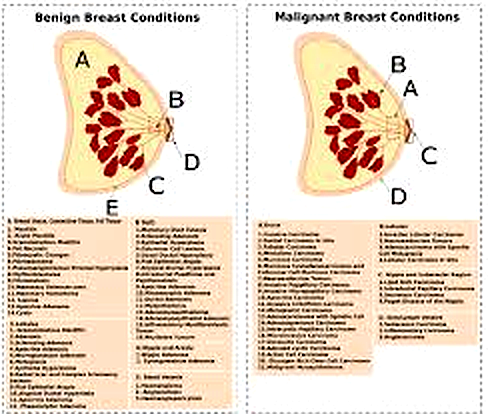

Common Causes of Breast Lumps

- Fibroadenoma (common in young women)

- Breast cysts

- Hormonal changes

- Infection or abscess

- Breast cancer (less common, but serious)